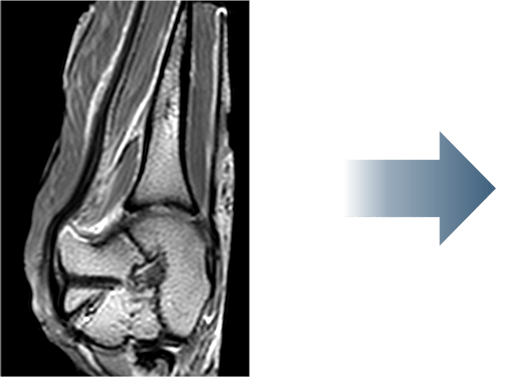

This is one of my cases, a 55-year-old woman, when her primary rotator cuff repair was done, we used Dermis on Demand, which is an allograft skin that can be utilized to help strengthen repairs. At four months out, the patient presented with pain and weakness following a traumatic injury and wound up re-tearing.

You can see a clear retear to the rotator cuff here with slight retraction, and some degeneration and thickness to the tendon.

This was not a softball case. Many aren’t. These are the complex rotator cuffs that worry you at night... Are you going to be able to fix it? Yes. But will it heal? That's the challenge. And that's where this implant helps you on a day-to-day basis.

We published this case study in the JOEI (Journal of Orthopedic Experience and Innovation) Journal. We did a revision of the large type-II repair and augmented it with BioBrace®. You can see the pre-op and three-month MRI below. Still fluid in the subacromial space but that tendon is clearly coming across into the footprint. Then, an eight-month MRI shows there's no further fluid in the subacromial space and maturation of that repair across the footprint.